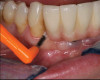

Fig 6. Customized oral hygiene to the implant-supported restoration with use of interdental brush;

Figure 6